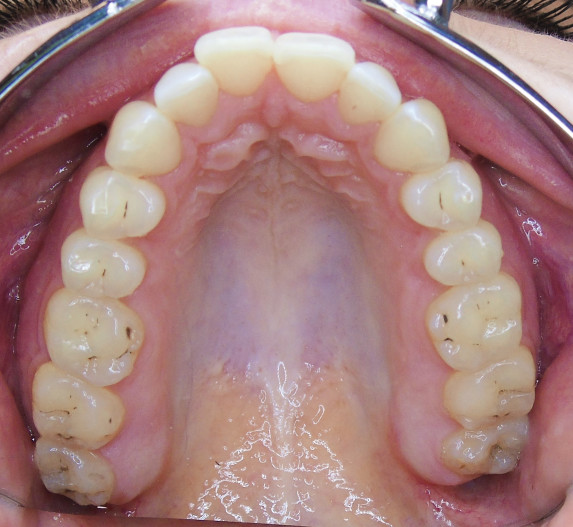

Der extraorale Befund (Abb. 1a–c) ergab ein gerades Durchschnittsgesicht mit leicht vergrößertem Nasolabialwinkel, ein symmetrisches Gesicht bei potenziell inkompetentem Lippenschluss sowie einen dolichofazialen Gesichtstyp. Intraoral lag beidseits annähernd eine Angle-Klasse I mit frontal offenem Biss (–2,5 mm) sowie ein dental-transversal zu schmaler Oberkiefer vor, woraus ein Kopfbiss von 13 und 23 resultierte. Des Weiteren zeigten sich ein persistierendes viszerales Schluckmuster und eine Inkongruenz der Kiefermitten (Abb. 2a–e; Abb. 3).

Die Patientin wurde über die möglichen Therapieoptionen der kombiniert kieferorthopädisch-kieferchirurgischen oder rein festsitzenden Therapie aufgeklärt, welche sie jedoch ablehnte. Ebenso lehnte die Patientin die Extraktion von vier Prämolaren ab. Somit fiel die Wahl auf die Behandlungsoption mit Alignern (SPARKTM System, Fa. Ormco). Nachdem die Patientin logopädisch behandelt und das viszerale Schluckmuster umgestellt worden war, konnte mit der Planung des Falls begonnen werden. Aufgrund der abgelehnten Therapieoptionen entfiel die Möglichkeit der Seitenzahnintrusion und man konzentrierte sich auf die Frontzahnextrusion als primäres Behandlungsziel.

Durch sogenannte Optimized-Extrusion-Attachments wurde eine Extrusion der oberen Frontzähne von max. 2,3 mm und der unteren Frontzähne von max. 1,4 mm geplant (Abb. 4a–c). Mithilfe einer leichten Expansion der Prämolarenregion konnte der Platzmangel im Oberkiefer ohne ASR kompensiert werden.